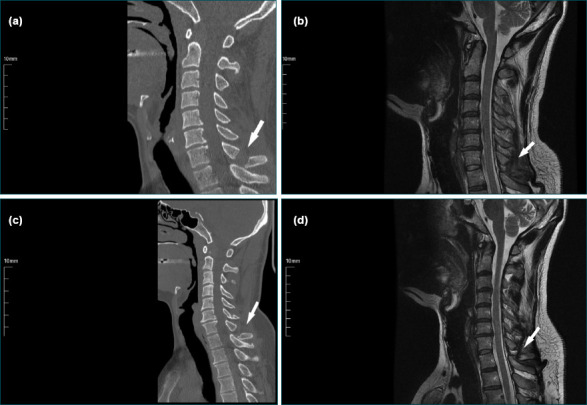

Results: A total of 44 patients (36 men and eight women) were included in the study, with a mean age of 43.1 years. Among them, 25 patients were admitted due to traffic accidents and 18 due to falls. Spinous process fractures were observed in 18, 17, and three patients in the cervical, thoracic, and lumbar regions, respectively. Multiple spinous process fractures were found in 15 patients, while six patients had fractures in both the cervical and thoracic regions (Clay-Shoveler's fracture). In 12 patients, spinal MRI with Short-TI Inversion Recovery (STIR) sequences was performed in addition to CT imaging. All patients with Clay-Shoveler's fracture fractures underwent both CT and MRI examinations. In all cases where MRI was performed, interspinous ligament damage was detected. However, no intracanal involvement or comorbid pathology was observed.

Conclusion: Notably, multiple fractures may occur, particularly at the cervicothoracic junction. Although spinous process fractures associated with trauma are rarely isolated, they are usually managed with medical treatment. Therefore, the vertebrae below the initially detected fracture site should also be evaluated. Additionally, imaging studies such as MRI with STIR sequences should be performed to assess ligament damage and the neural canal, in addition to tests for evaluating bony structures.